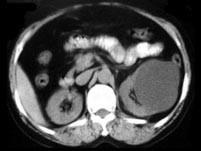

问题 女,55岁,发热,左侧腰部痛胀不适4天,CT检查如图所示,下列说法错误的是 ( )

选项 A、考虑为多囊肾合并感染 B、考虑为多发肾囊肿合并感染 C、病灶境界清晰,囊内密度近似水的密度 D、肾前筋膜增厚 E、左肾上极和下极各可见一个类圆形的囊性病灶

答案 A